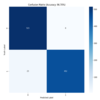

We have developped cutting-edge AI (Classification, Regression, Segmentation) models and Machine Learning algorithms to address critical challenges across a broad spectrum of diseases,

including: different types of cancer, Alzheimer's disease and diabetes.

We have developped cutting-edge AI (Classification, Regression, Segmentation) models and Machine Learning algorithms to address critical challenges across a broad spectrum of diseases,

including: different types of cancer, Alzheimer's disease and diabetes. a revolution?